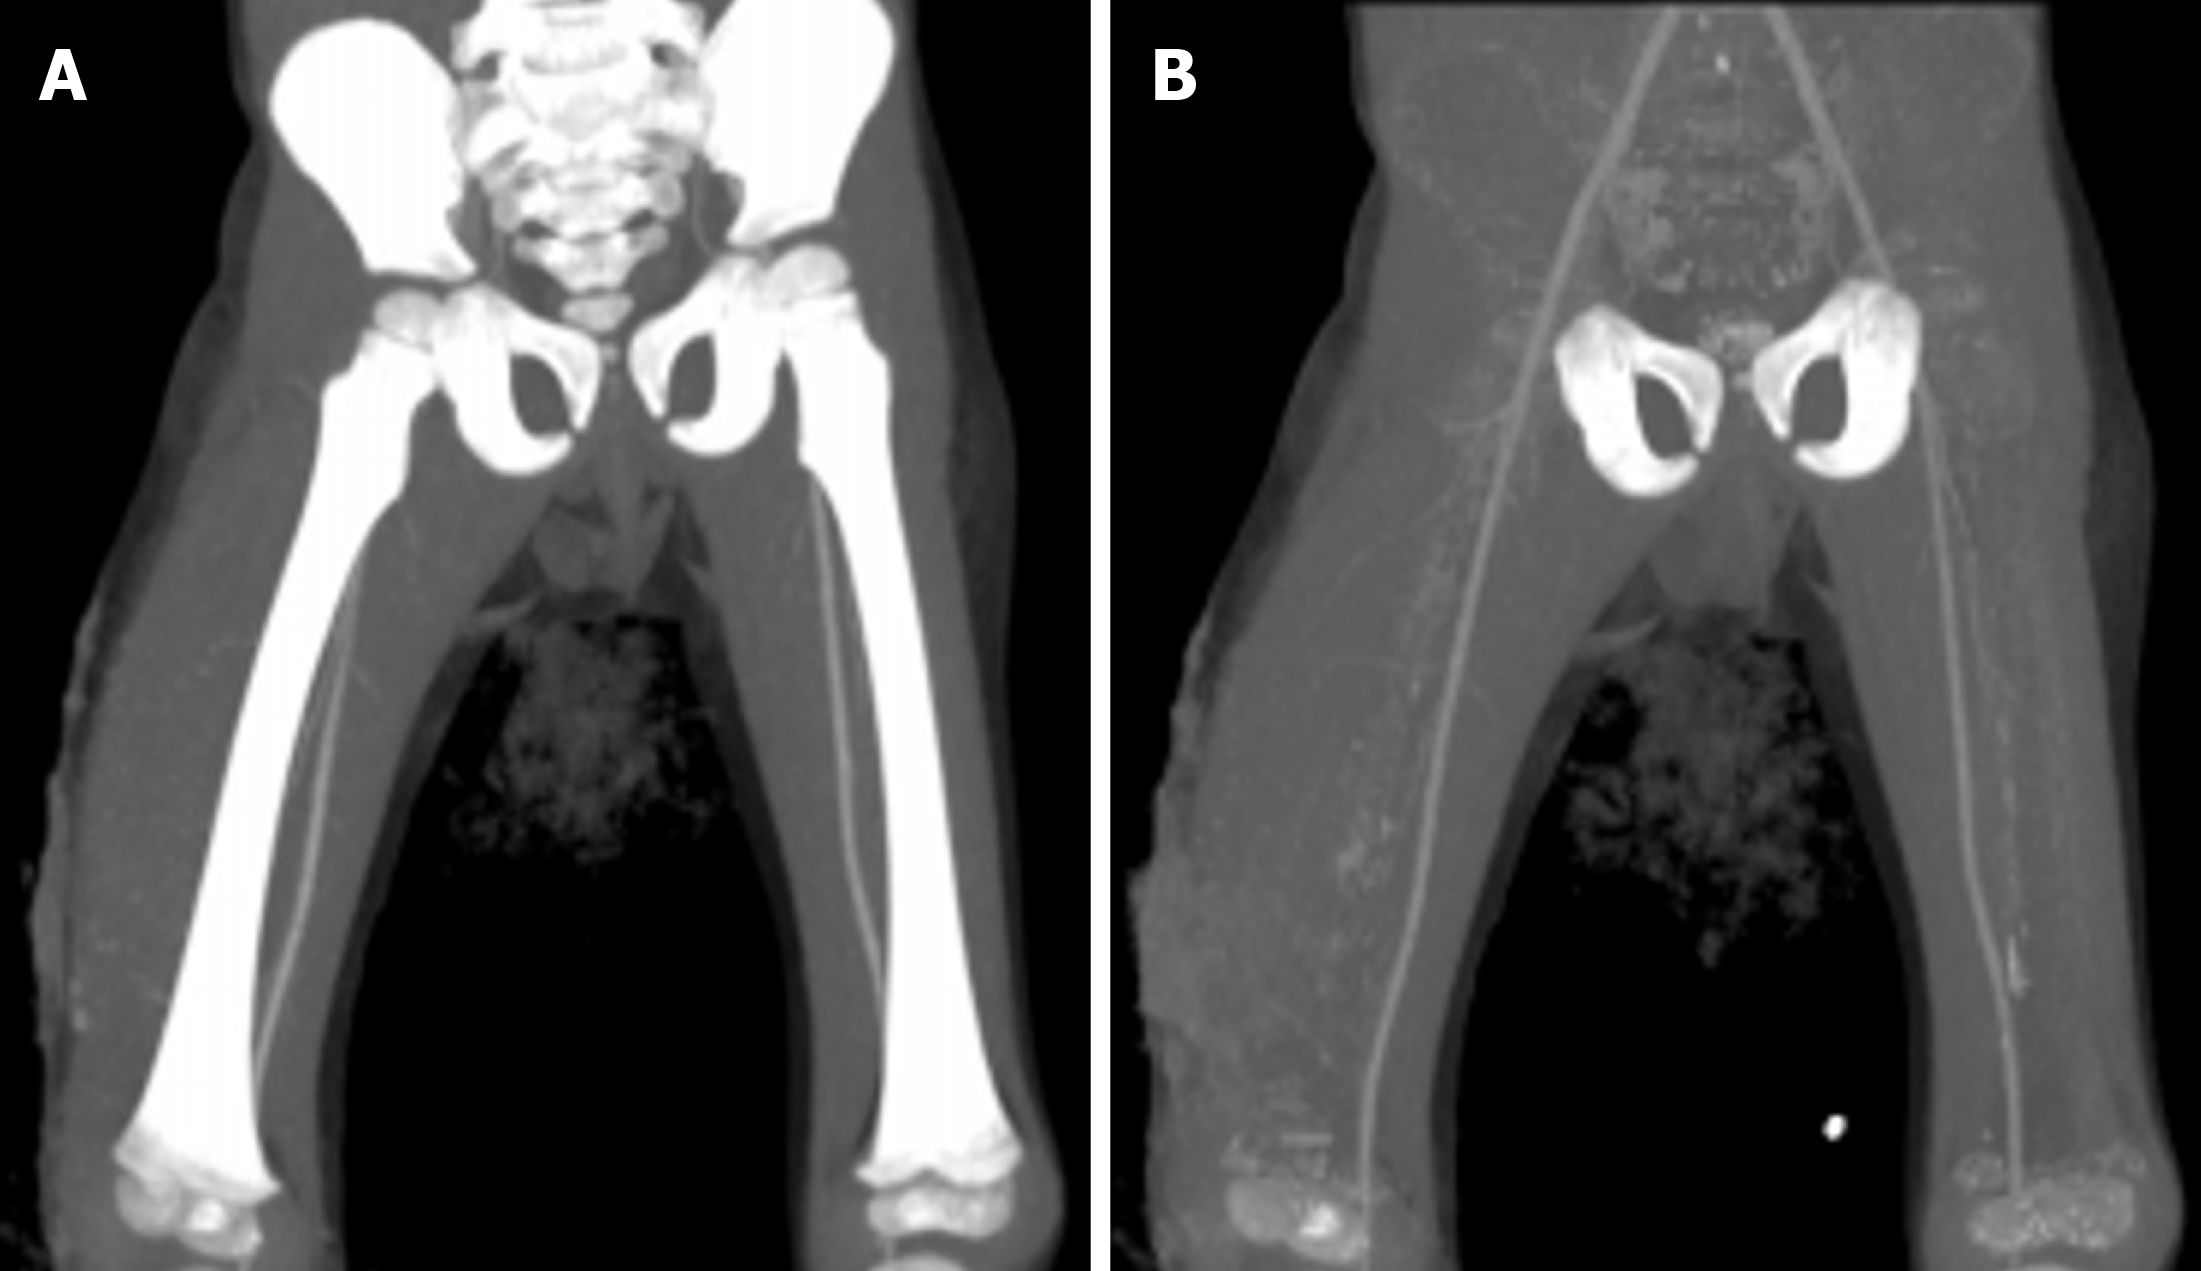

Figure 5 A 4-year-old male with trauma.

Coronal images of CT angiography of bilateral lower limb vessels to show the automated bone removal application of dual energy CT. A: Coronal maximum-intensity projection image showed bilateral superficial femoral arteries overlapped by bones, along with soft tissue swelling along the right thigh; B: Application of the bone removal tool of dual-energy CT enabled better delineation of the arteries and confirmed the absence of any pseudoaneurysm.